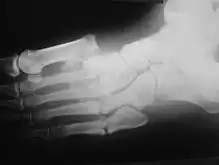

Radiologic findings

First, it is important to recognize that two types of abnormality may be detected. One is termed atrophic, in which there is osteolysis of the distal metatarsals in the forefoot. The more common form of destruction is hypertrophic joint disease, characterized by acute peri-articular fracture and joint dislocation. According to Yochum and Rowe, the "6 D's" of hypertrophy are:

- Distended joint

- Density increase

- Debris production

- Dislocation

- Disorganization

- Destruction

The natural history of the joint destruction process has a classification scheme of its own, offered by Eichenholtz decades ago:

Stage 0: Clinically, there is joint edema, but radiographs are negative. A bone scan may be positive before a radiograph is, making it a sensitive but not very specific modality.

Stage 1: Osseous fragmentation with joint dislocation seen on radiograph ("acute Charcot").

Stage 2: Decreased local edema, with coalescence of fragments and absorption of fine bone debris.

Stage 3: No local edema, with consolidation and remodeling (albeit deformed) of fracture fragments. The foot is now stable.

Atrophic features:

- "Licked candy stick" appearance, commonly seen at the distal aspect of the metatarsals

- Diabetic osteolysis

- Bone resorption